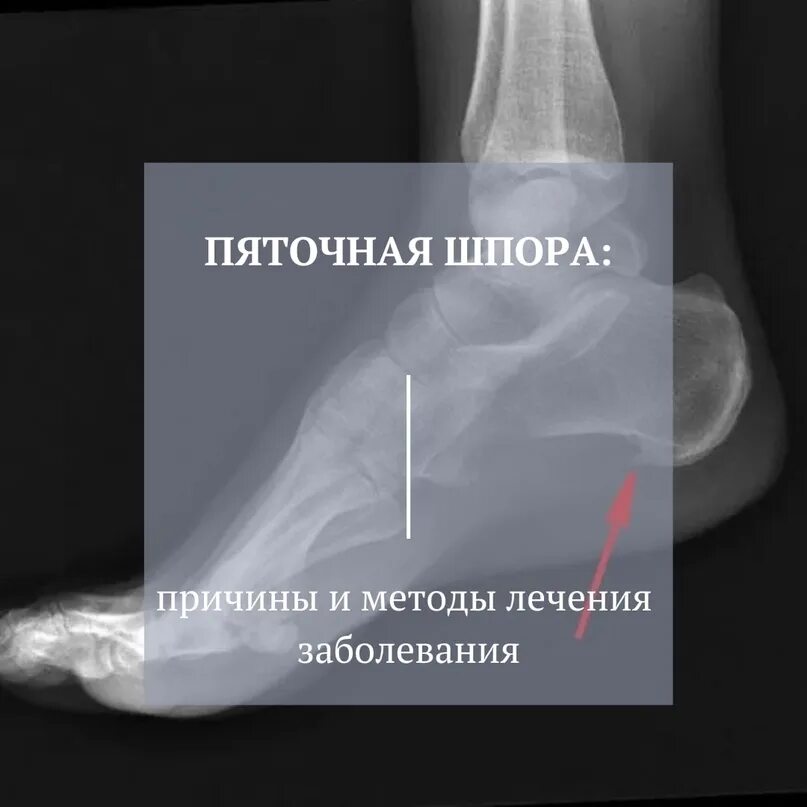

Почему появляется шпора причины